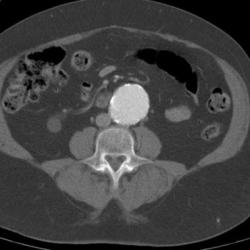

CT scanning accurately demonstrates dilation of the aorta and involvement of major branch vessels proximally and distally. This information helps in determining the appropriate intervention, which may be either surgical or endovascular repair. (See the image below.)